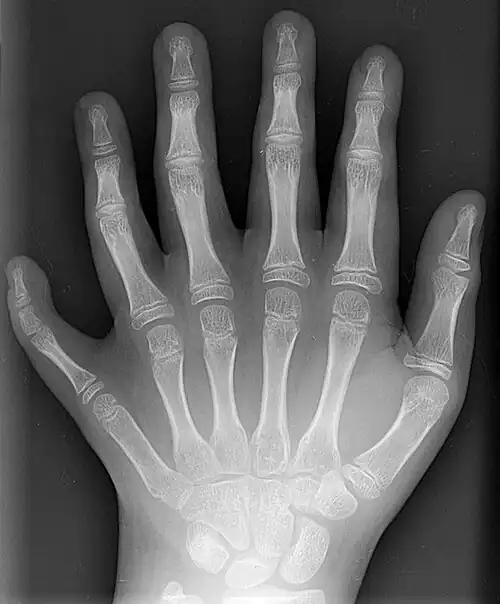

Clinical significance

X-ray of the left hand of a ten-year-old boy with polydactyly

A number of genetic disorders affect the hand. Polydactyly is the presence of more than the usual number of fingers. One of the disorders that can cause this is Catel-Manzke syndrome. The fingers may be fused in a disorder known as syndactyly. Or there may be an absence of one or more central fingers—a condition known as ectrodactyly. Additionally, some people are born without one or both hands (amelia). Hereditary multiple exostoses of the forearm—also known as hereditary multiple osteochondromas—is another cause of hand and forearm deformity in children and adults.[21]